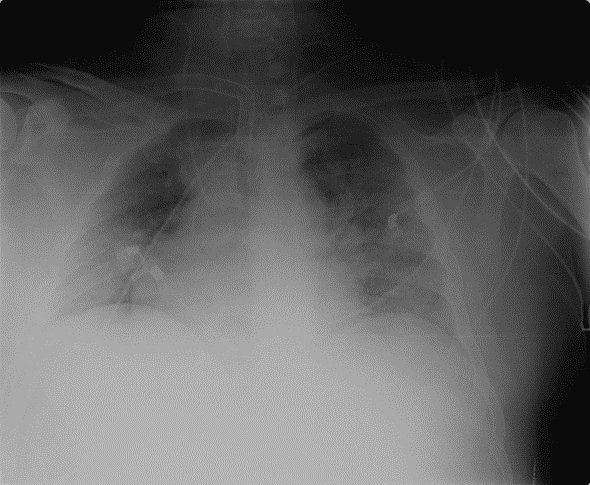

- Chest X-rays showed bilateral condensation. Suspicion of nosocomial pneumonia led to a change in antibiotic treatment and a CT scan was performed to rule out intra-abdominal complications.

This CT scan shows pancreatitis with pancreatic and peripancreatic necrosis but no new complications. What is seen is the splenic infarction, which was already visualised after the splenic vein thrombosis.

The diagnosis concluded with nosocomial pneumonia and sepsis of respiratory origin, arterial blood gas analysis was performed again and again revealed acidosis.